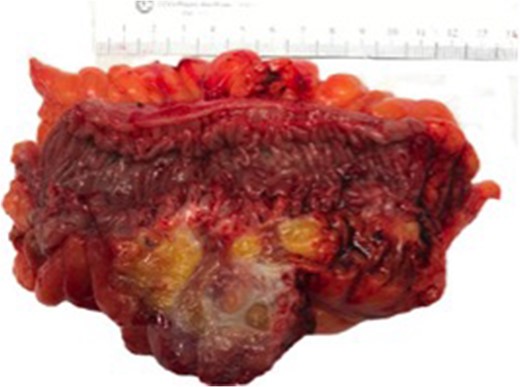

Pathologic exam revealed a resected portion of rectosigmoid that contained a diverticulum that had fistulized into the attached ovarian tissue, seen in Fig. 5. An adherent portion of fallopian tube was also present. The fistula tract was lined by granulation tissue with acute and chronic inflammatory cells and focal foreign body giant cells as seen in Fig. 6. The fistula extended into the ovarian stroma, causing a focal tuboovarian abscess. No other diverticula were present.

Gross photograph showing colonic diverticulum extending into pericolonic fat and forming a fistula to the underlying ovarian tissue.